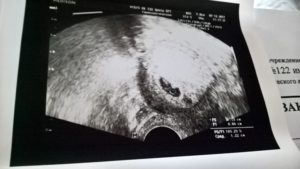

В 25% случаев из 60% удачных результатов ЭКО развивается многоплодие. Это случается по причине того, что женщине подсаживают сразу несколько эмбрионов для увеличения шансов на беременность. Иногда один зародыш не приживается, а второй успешно имплантирует и продолжает развитие.

Часто приживаются все, и тогда, по желанию родителей, врачи могут изъять лишние эмбрионы. Но сделать это необходимо на самых ранних сроках, поэтому точное определение количества эмбрионов так важно. Узнать точное количество возможно только с помощью ультразвукового обследования.

В 10% случаев возникает внематочная беременность, поэтому второй важный показатель при ЭКО — место прикрепления эмбриона. Если гормональная терапия проводилась правильно, плод имплантирует в эндометрий матки.

Но если имеются какие-либо нарушения в гормональном фоне женщины или в ее репродуктивных органах, зародыш может закрепиться в маточной трубе либо пойти еще дальше и остановиться возле яичника, в брюшной полости. Такая патология на первых этапах не проявляет себя, поэтому нужна более точная диагностика. Первое ультразвуковое обследование поможет избежать осложнений и вовремя устранить последствия.